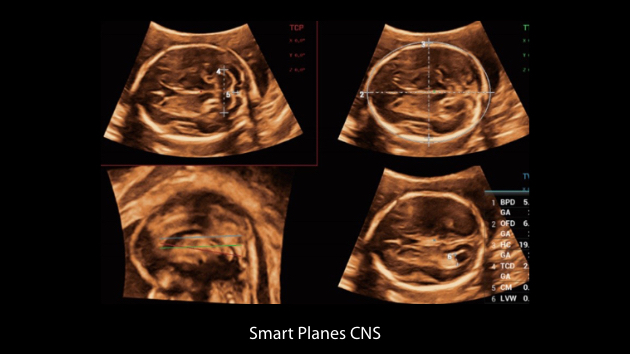

El sistema Nuewa I9, dise?ado exclusivamente para la atenciĂłn mĂ©dica neonatal y de mujeres, brinda una experiencia innovadora integral. Estas innovaciones se desarrollan sobre la base de un conocimiento profundo de situaciones clĂnicas complejas para proporcionar respuestas precisas y oportunas, una gran eficiencia y una experiencia de usuario extraordinaria.

La plataforma ZST+?es una innovaciĂłn extraordinaria que representa toda una evoluciĂłn en el ĂĄmbito de la ecografĂa. Transforma las mĂ©tricas ecogrĂĄficas de la formaciĂłn de haces convencional al procesamiento basado en datos de canal. Supera la limitaciĂłn tradicional de tener que equilibrar entre resoluciĂłn espacial, resoluciĂłn temporal y uniformidad del tejido, con lo que ofrece una calidad de imagen excepcional para soluciones de producciĂłn de imĂĄgenes infinitas con mejoras continuas.